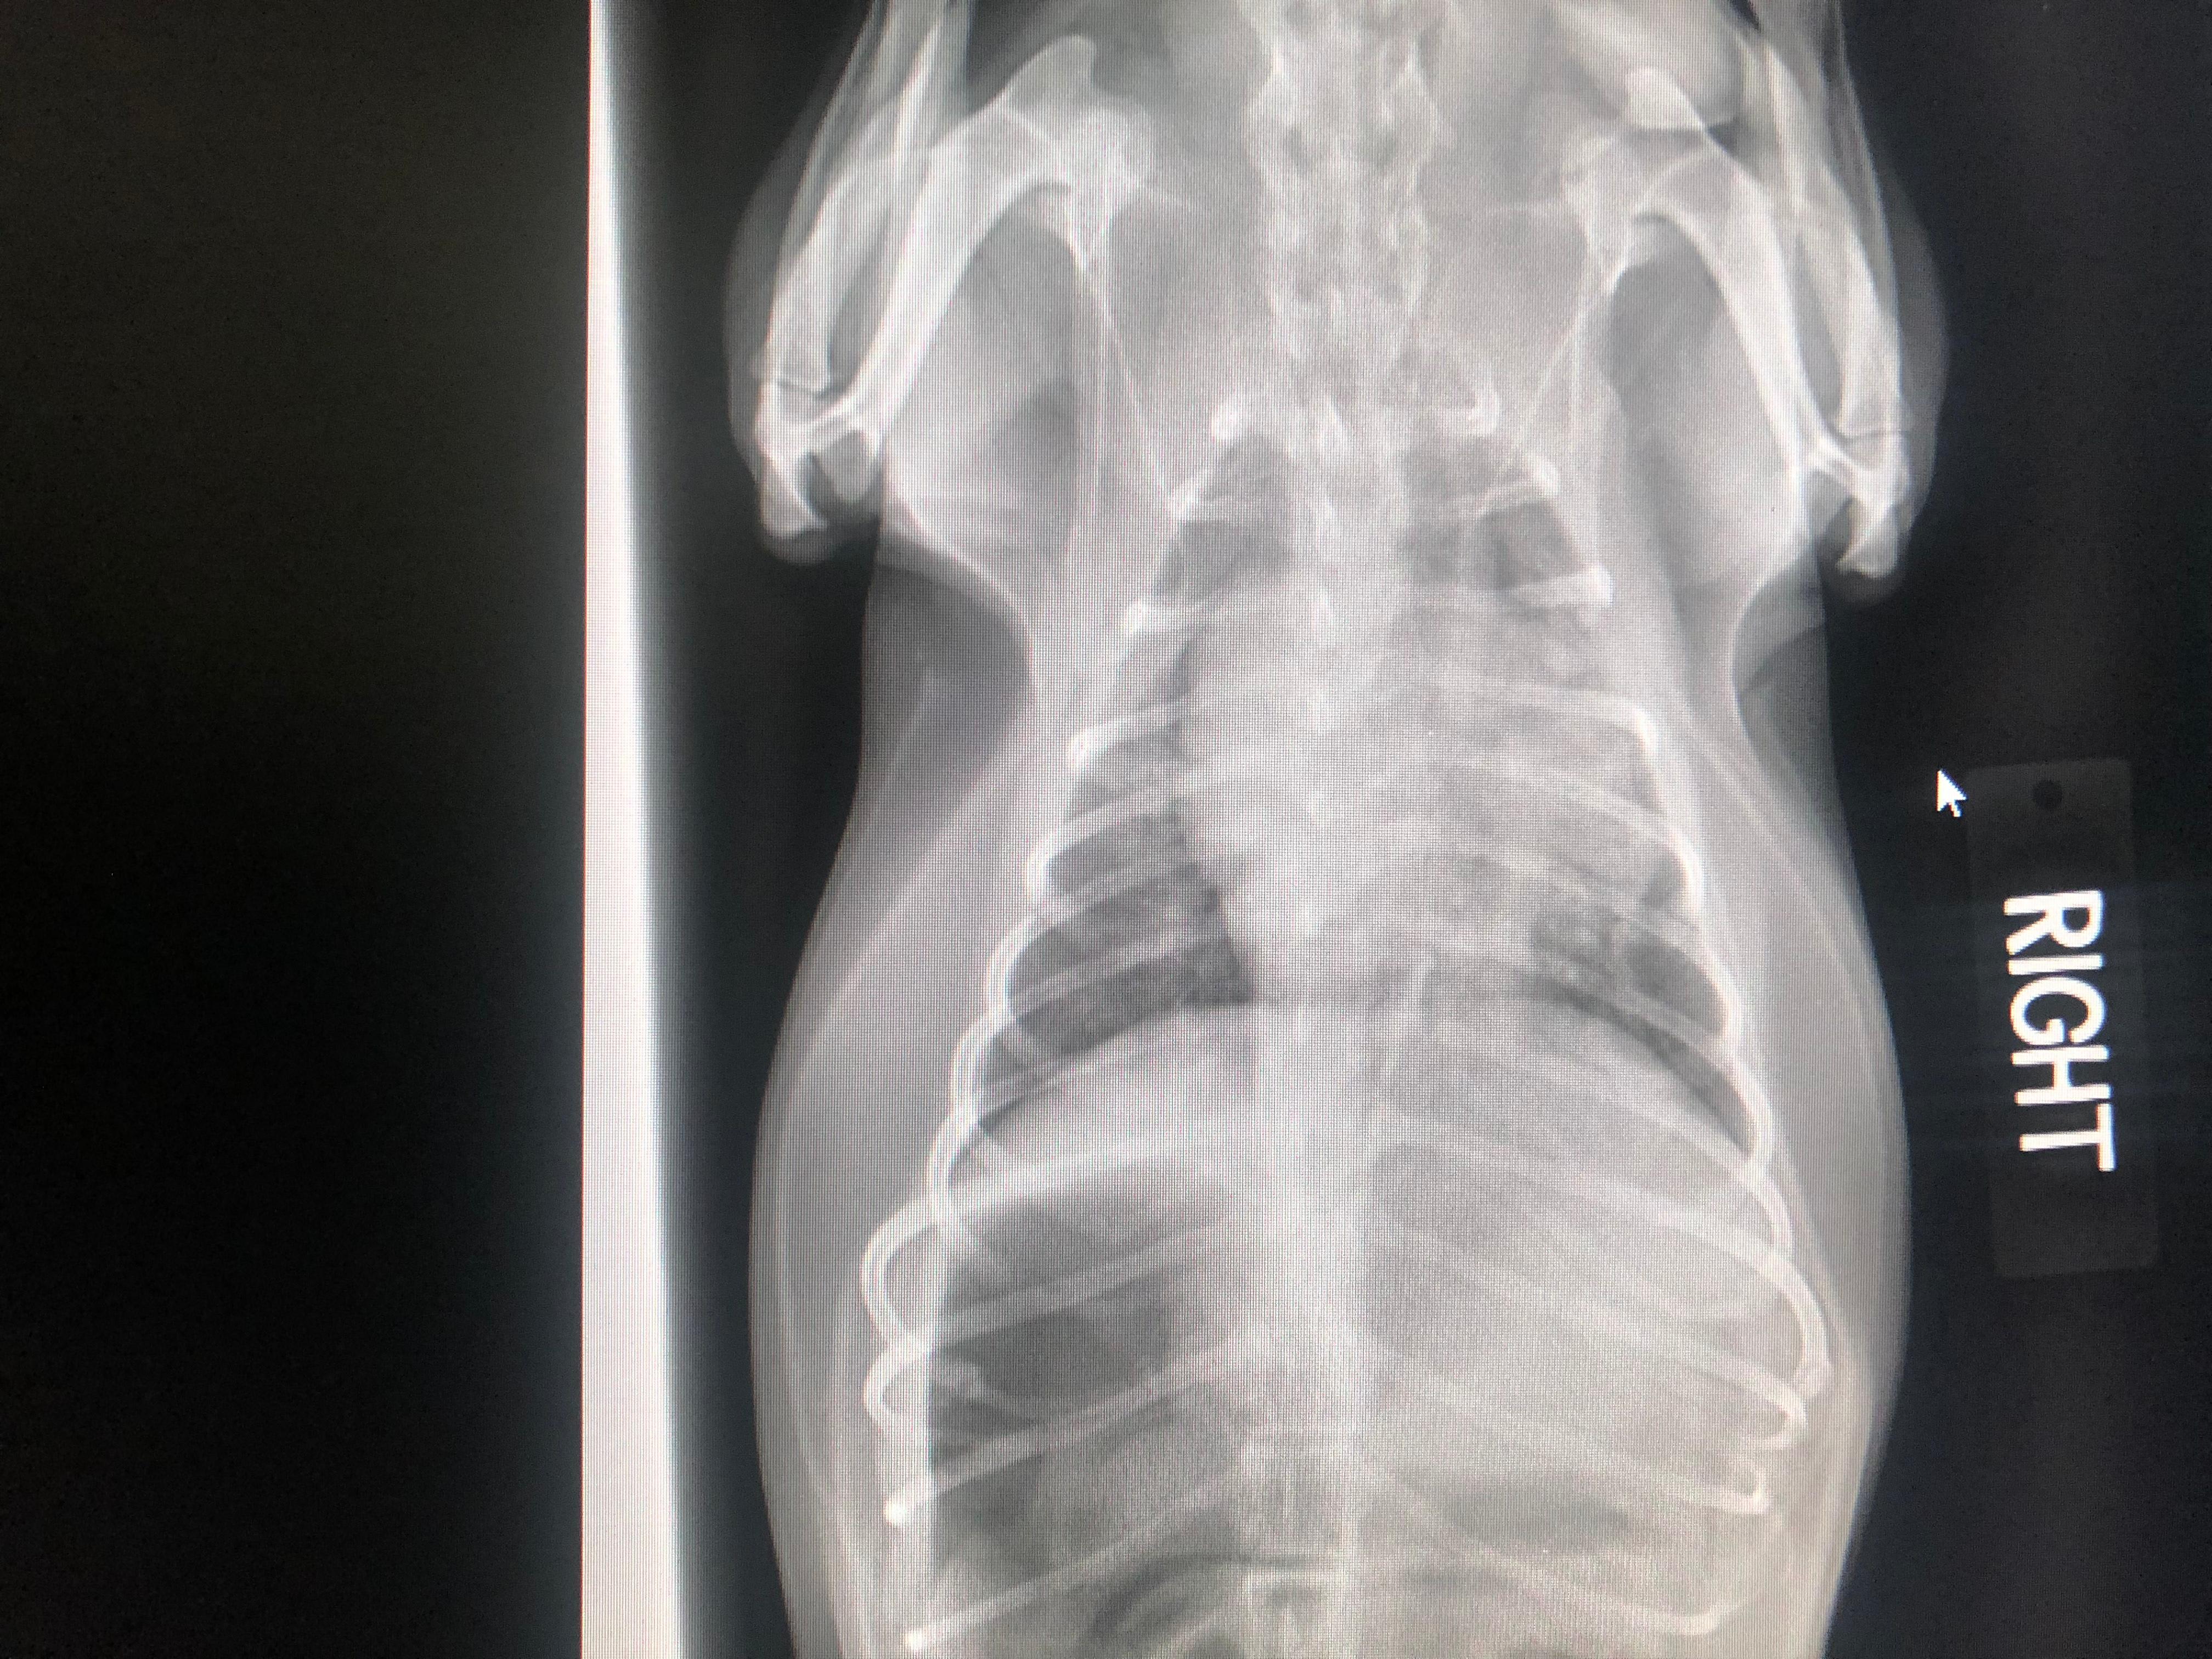

My dog recently died, the vet still doesn’t know the cause. While we’re grieving we borrowed our other dog from my step family, she’s come home with us but now she vomited, just like my other dog did when she first got sick. Daisy, my step family’s dog, ate grass from outside and just coughed foam into her water. I’ve attached the X-ray from Lucy, my dog who has just passed, during her final times. Can you tell me if Daisy could get this too, or what she has? I really can’t handle losing her too

Hi, from the x-rays Lucy seemed to have an enlarged heart wether it was just a cardiomyopathy or possibly a mass in her right chest it is impossible to tell. From these xrays I can tell you that Lucy s condition was not contagious, but most likely cardio-respiratory in its origin. I would have Diasy’s Chest checked over but I would try not to worry too much, sending you positive thoughts.